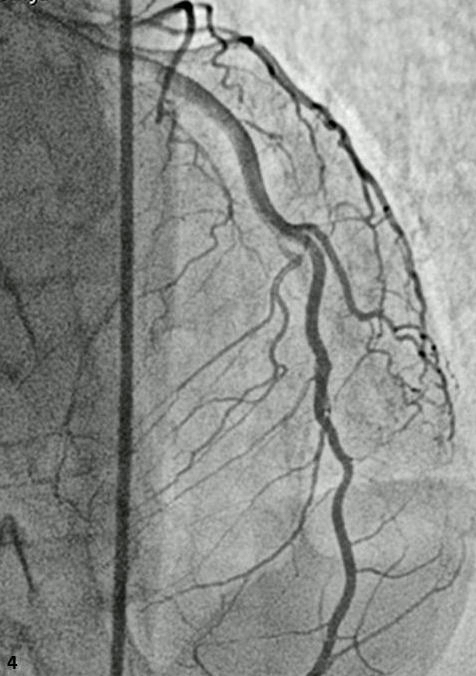

Abstract PDF ECG 1 Angio 1 Angio 2 Angio 3 Angio 4 ECG 2 Table Chart Original File 1 2 3 4 5 6 Reply to reviewer Fig. 1. ECG during myocardial infarction Fig. 2. Coronary angiography of LCA during myocardial infarction Fig. 3. Coronary angiography of LCA during myocardial infarction Fig. 3a. Coronary angiography of LCA during myocardial infarction Fig. 4. Coronary angiography of LCA 2 years after myocardial infarction Fig. 5. Coronary angiography of LCA 2 years after myocardial infarction Fig. 6. ECG 2 years after myocardial infarction Fig. 7. Thrombolytic trials in patients with coronary artery dissection Fig. 8. Flow chart of the study selection process -